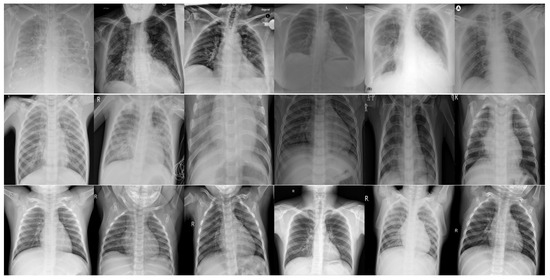

3.1. Chest X-ray Dataset

3.2. Synthetic Data Generation through Conditional DC-GAN